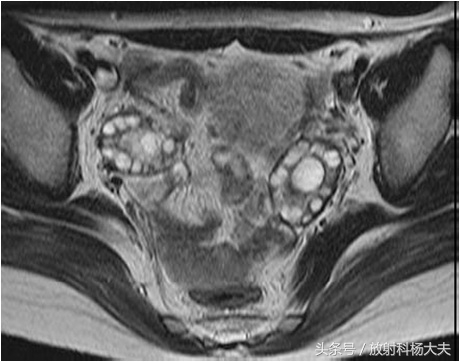

MRI属于无创检查,做过MRI的朋友都知道,患者只需要在那躺着,各项检查就这么神不知鬼不觉的完成了。而且MRI对人体没有任何电离辐射,这点尤其适合那些年轻的或者想生育的女性朋友们。MRI对软组织有极好的分辨率,可以通过多参数成像提供丰富的诊断信息,而且可以通过多角度成像选择各种剖面,获得其他成像技术所不能或难以获得角度的图像。卵巢是位于子宫两侧的一对卵圆形的生殖器官。正常卵巢信号在 T1WI上为均匀的中等或稍低信号强度,内部结构不易分辨。T2WI序列表现为多个大小不一的小圆形或小卵圆形的,均匀高信号囊性结构,囊内信号与液体一致,位于卵巢皮质内,典型呈花环样排列,以T2WI压脂序列显示最清晰。囊壁在 T1WI表现为等信号,T2WI囊壁较T1WI显示清晰,呈均匀的等低信号。在生育年龄妇女,卵巢髓质内含有大量富含血管的疏松结缔组织,T2WI上也表现为稍高信号。正常女性单侧卵巢卵泡数目6~7个,一般不超过10个,正常卵巢体积约6~7 cm3大小。在排卵期,优势卵泡的直径最大可达2 cm。多囊卵巢综合症患者的卵巢 MRI信号与正常卵巢一致,而卵巢体积较正常卵巢增大,卵泡数目较正常增多,卵泡排列无特别规律,可沿周边分布,亦可弥漫分布。与正常女性相比,多囊卵巢综合症患者双侧卵巢较正常卵巢增大2~3倍,卵巢内可见许多闭锁卵泡和处于不同发育期的卵泡,但无成熟卵泡生成及排卵迹象。